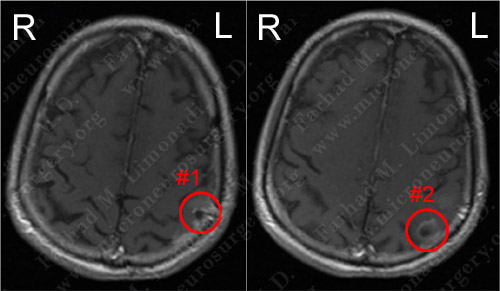

MRI scan of the patient's brain showed two contrast-enhancing tumors in close proximity to each other.